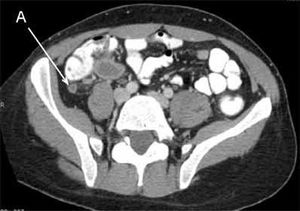

This CT scan(Arrow.A) shows an inflammed appendix without perforation of A 34-year-old woman presented with nausea, vomiting, constipation, and periumbilical pain that settles in the lower right quadrant. On physical exam, she had tenderness and guarding in the lower right quadrant. Treatment map is cefoxitin in case if possibility for perforation exists, and the definitive treatment would be appendectomy.